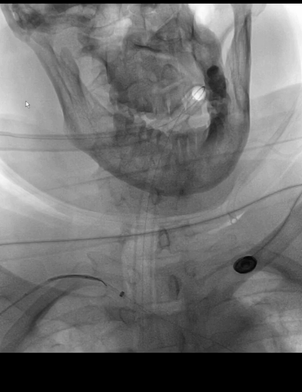

经微导管送入一4*20mm取栓支架(S AB),释放支架后造影示闭塞再通,支架头端恰好位于基底动脉远端。

考虑到双胚胎后交通,基底动脉管径一般比较小,故回收取栓支架时6F中间管只是行至基底动脉近端,未敢深入其中。

取栓后造影示:基底动脉再通,如之前预判,其管径确实细小;同时造影剂逆流至左椎动脉V4段,显示其管径明显纤细。